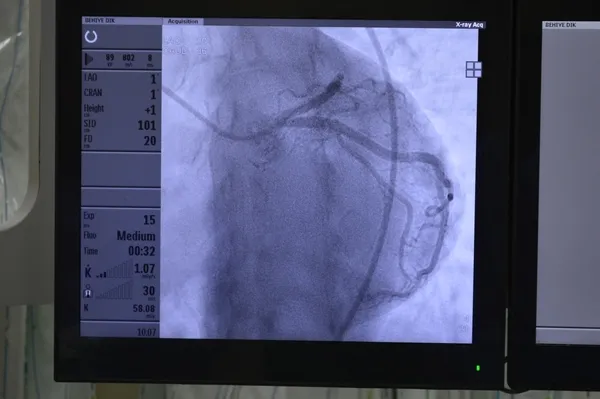

Pulmoner Hipertansiyon, akciğer damarlarında kan basıncı artışı ile seyreden, zamanında doğru tedavi edilmediği taktirde kalp yetersizliği ve ölümle sonuçlanan ciddi bir kalp-akciğer dolaşım bozukluğu hastalığı. Yüksek tansiyonla karıştırılması gereken bu hastalık doğası gereği oldukça kompleks bir hastalık olup kesin tanısı sadece uzman merkezlerde ve anjiyografik yöntemle konuluyor. Her yaş grubundaki insanı etkileyebilen pulmoner hipertansiyon erkeklere nazaran kadınlarda 1.8 kat daha fazla görülüyor. Hastalarda nefes darlığı, yorgunluk, göğüs ağrısı, ödem, baş dönmesi, çarpıntı ve ses kısıklığı gibi belirtiler gösteren hastalıkta zamanında ve doğru bir tedavi stratejisi uygulanmadığında gelişen kalp yetersizliği ölümle sonuçlanabiliyor. 5 Mayıs Dünya Pulmoner Hipertansiyon Günü kapsamında Türk Kardiyoloji Derneği Pulmoner Vasküler ve Erişkin Doğumsal Kalp Hastalıkları Çalışma Grubu tarafından pulmoner hipertansiyonlu hastalar ile ilgili farkındalığı artırmaya yönelik çeşitli etkinlikler düzenlenerek pulmoner hipertansiyonlu hastaların tanısını mümkün olduğunca erken zamanda koymak ve uygun tedavi stratejileri ile daha uzun ve kaliteli bir yaşam şansı sunmaya çalışıyor.